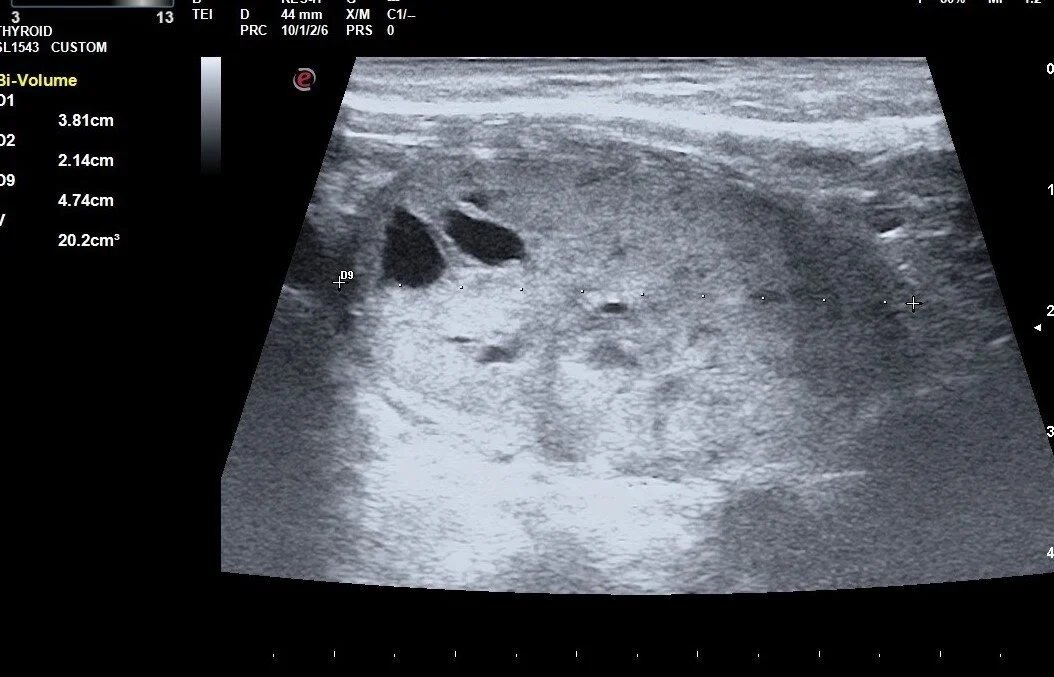

This case shows effect of 2 treatments on a large nodule and the correlation between volume reduction and normalization of thyroid levels

Ablation is accomplished by the dissipation of heat (produced by high-frequency radio waves) from the tip of a special water-cooled needle. Specialized white blood cells subsequently remove the dead nodule tissue in the weeks, and months following RFA, which causes the nodule to shrink considerably. Large-scale studies have shown an average reduction in nodule volume of approximately 60% after 3 months, and of 80% after one year, depending on the original nodule size and composition.

Most studies have suggested that nodules less than 10-12 mL in volume have a better chance of normalizing TFTs with 1 session of RFA